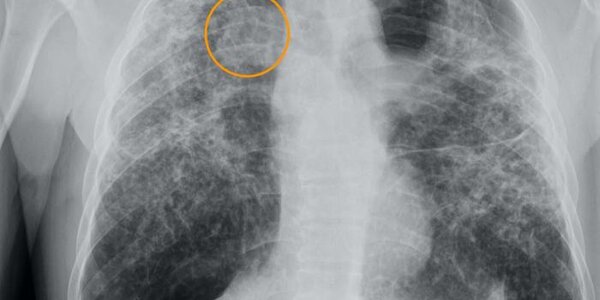

Even After Getting Cancer, Quitting Cigarettes Leads To Greater Longevity

Cigarettes are the top lifestyle risk factor for getting cancer, though alcohol and obesity have begun to close the gap as awareness of the risks of cigarettes, coupled with more nicotine smoking cessation and harm reduction tools, have caused cigarette use to decline. Even if you get cancer, quitting smoking improves outcomes.  A new analysis found a 22-26% reduction in cancer-related mortality among those who had quit smoking within three months of using smoking cessation and harm reduction techniques. The best outcomes were observed in patients who were abstinent from smoking three…